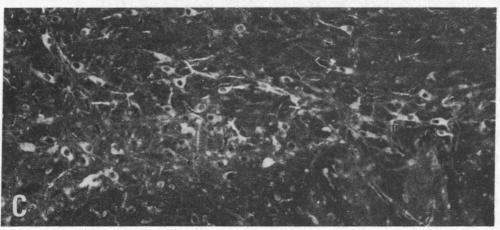

Antibodies raised against a synthetic deca-peptide corresponding to a specific sequence of Gi3-alpha protein (an inhibitory guanine nucleotide-binding protein) were used to analyze Gi3-alpha-like immunoreactivity in brain sections from colchicine-treated rats by indirect immunofluorescence histochemistry. Gi3-alpha-peptide-positive cell bodies were found in the ventral tegmental area and substantia nigra, and these cells were also cholecystokinin (CCK)- and tyrosine 3-hydroxylase-positive. Gi3-alpha-peptide staining was observed in perikarya in the hippocampus and in fibers in the nucleus accumbens, tuberculum olfactorium, bed nucleus of stria terminalis, and a spino-thalamic tract, where it coexisted with CCK-like immunoreactivity as well. No coexistence with CCK occurred in Gi3-alpha-peptide-positive ependymal cells outlining the aqueduct and ventricles. Preadsorption of Gi3-alpha antibodies with CCK-8 or CCK-33 did not alter Gi3-alpha-peptide staining. The occurrence of Gi3-alpha-peptide-like immunoreactivity in CCK-containing neurons may indicate the presence of Gi3-alpha protein and in CCK/dopamine neurons may indicate an association of this Gi protein with dopamine autoreceptors.

利用针对与Gi3-α蛋白(一种抑制性鸟嘌呤核苷酸结合蛋白)特定序列相对应的合成十肽产生的抗体,通过间接免疫荧光组织化学分析秋水仙碱处理大鼠脑切片中的Gi3-α样免疫反应性。在腹侧被盖区和黑质中发现了Gi3-α肽阳性细胞体,这些细胞也是胆囊收缩素(CCK)和酪氨酸3-羟化酶阳性的。在海马的核周体以及伏隔核、嗅结节、终纹床核和脊髓丘脑束的纤维中观察到Gi3-α肽染色,在这些部位它也与CCK样免疫反应性共存。在围绕导水管和脑室的Gi3-α肽阳性室管膜细胞中未发现与CCK共存。用CCK-8或CCK-33对Gi3-α抗体进行预吸附不会改变Gi3-α肽染色。在含CCK的神经元中出现Gi3-α肽样免疫反应性可能表明存在Gi3-α蛋白,而在CCK/多巴胺神经元中出现可能表明这种Gi蛋白与多巴胺自身受体有关联。